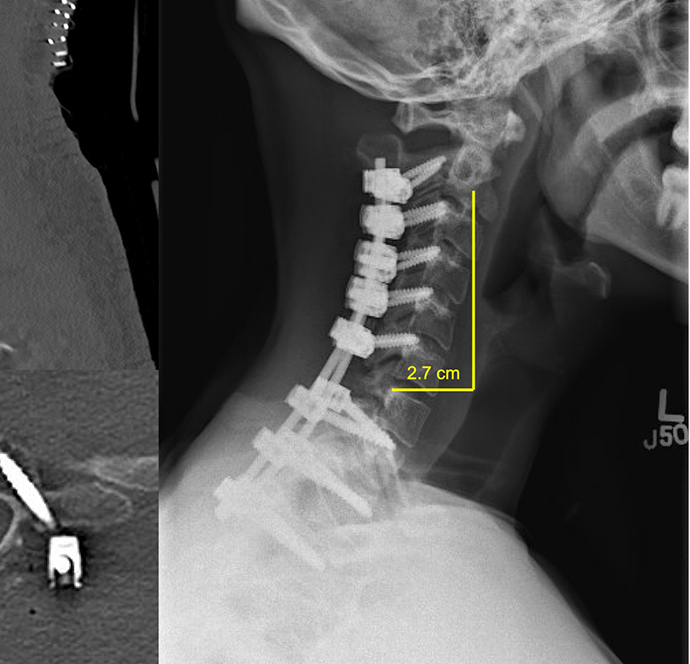

Cervical deformity